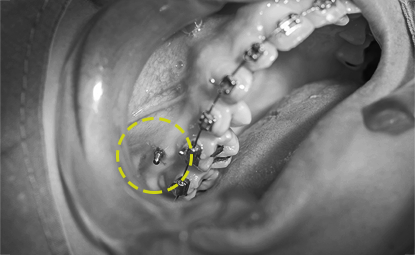

미니스크류를 통한 급속교정

미니스크류는 임플란트의 작은 형태로 간단한 국소마취 후 시술되며, 여러가지 어려운 치아이동을 자유롭게 해줍니다.

특히 돌출입교정에 효과적이며, 치아교정만으로도 외모적인 개선이 가능합니다.